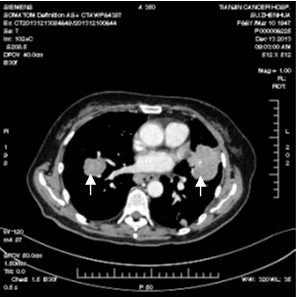

安罗替尼是一种作用于肿瘤细胞内多个靶点的抗癌新药,可通过诱导细胞凋亡杀死主要肿瘤,还可通过抑制肿瘤新生血管生成、断绝其营养供应而“饿死”残余肿瘤。由于其独特的抗癌机制,其对已抗拒传统药物的肿瘤细胞仍可能有效、从而为接受三线及以上治疗的患者带来了希望。在目前进行的试验中,一例有双肺转移、已经历六种治疗、肿瘤依然进展的患者在安罗替尼治疗三周后双肺病灶缩小累积接近50%,取得了既往治疗未达到过的效果。

治疗前的双肺肿瘤(箭头所示)